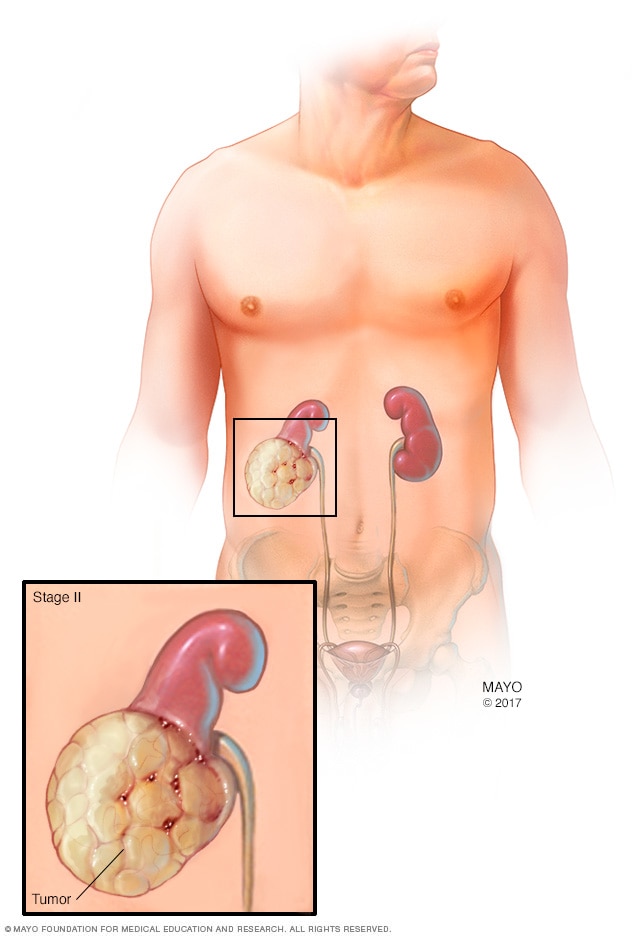

Stage 2 kidney cancer

A stage 2 kidney cancer means that the tumor in the kidney is larger than 2 3/4 inches (7 centimeters) in diameter, but it's still confined to the kidney.

The stages of kidney cancer range from 1 to 4. A stage 1 kidney cancer is small and confined to the kidney. As the cancer gets larger, the stages get higher. A stage 4 kidney cancer has grown beyond the kidney or spread to other parts of the body.